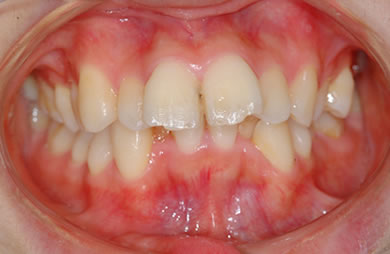

| 主訴 | 上下乱ぐい歯と出っ歯を治したい。 | ||||||||||||||||||||||||||||||||

| 治療方針 | 口元が出ていていること、がたつきが大きいことより、上下左右の第一小臼歯および親知らずを抜歯し、マルチブラケット治療を行う。抜歯した隙間を活用できるよう上顎にはインプラントアンカー(釘)を使用し、その釘より歯を後ろに移動する。 | ||||||||||||||||||||||||||||||||

| 治療内容 | 唇側矯正(シルバー)、矯正用スピードインプラント、ハイブリッドセラミックインレー2本 | ||||||||||||||||||||||||||||||||